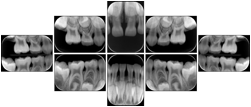

Intra-oral radiography typically involves acquisition of multiple images of various parts of the dentition. Many digital radiographic systems offer customized templates that are used for displaying the images in a study on the screen. These templates may also be referred to as mounts or view sets. The Structured Display Object represents a standard method of encoding and exchanging the layout and intended display of Structured Displays. A structured display object created in this manner could be stored with a study and exchanged with images to allow for complete reproduction of the original exam.

3. A dental provider wishes to capture a series of DICOM IO images for the patient’s dentition. The tooth morphology, teeth are divided into molars, premolars, canines and incisors, and a number of images for each jaw. The anatomic information was captured utilizing the triplet of schema. This standard code sequence is based on ISO 3950-2010, Dentistry - Designation system for teeth and areas of the oral cavity.

Every IO image should have anatomic information either through the primary or modifier sequence.

In most standard cases, images are oriented in structured layouts. These structured displays are useful to be shared between providers for reference purposes.

Table OO.1.1-1 shows structured display standard templates, where Viewset ID is based on the Japanese Society for Oral and Maxillofacial Radiology (JSOMR) classification provided by JIRA (Japan Medical Imaging and Radiological Systems Industries Association, www.jira-net.or.jp). Expected or typical teeth to be imaged location, region and designation codes are based on ISO 3950-2010, Dentistry - Designation system for teeth and areas of the oral cavity. For all the hanging protocols listed in OO.1.1-1, the value to use for Hanging Protocol Creator (0072,0008) is "JSOMR" and the value to use for Hanging Protocol Name (0072,0002) does not include "JSOMR" (e.g., "DL-S001A", not "JSOMR DL-S001A").